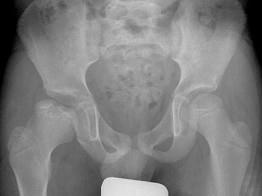

问题 男,6岁,髋痛、跛行,请结合CR检查,选出最可能的诊断 ( )

选项 A、骨囊肿 B、软骨肉瘤 C、股骨头骨骺缺血坏死 D、骨肉瘤 E、髋关节结核

答案 C